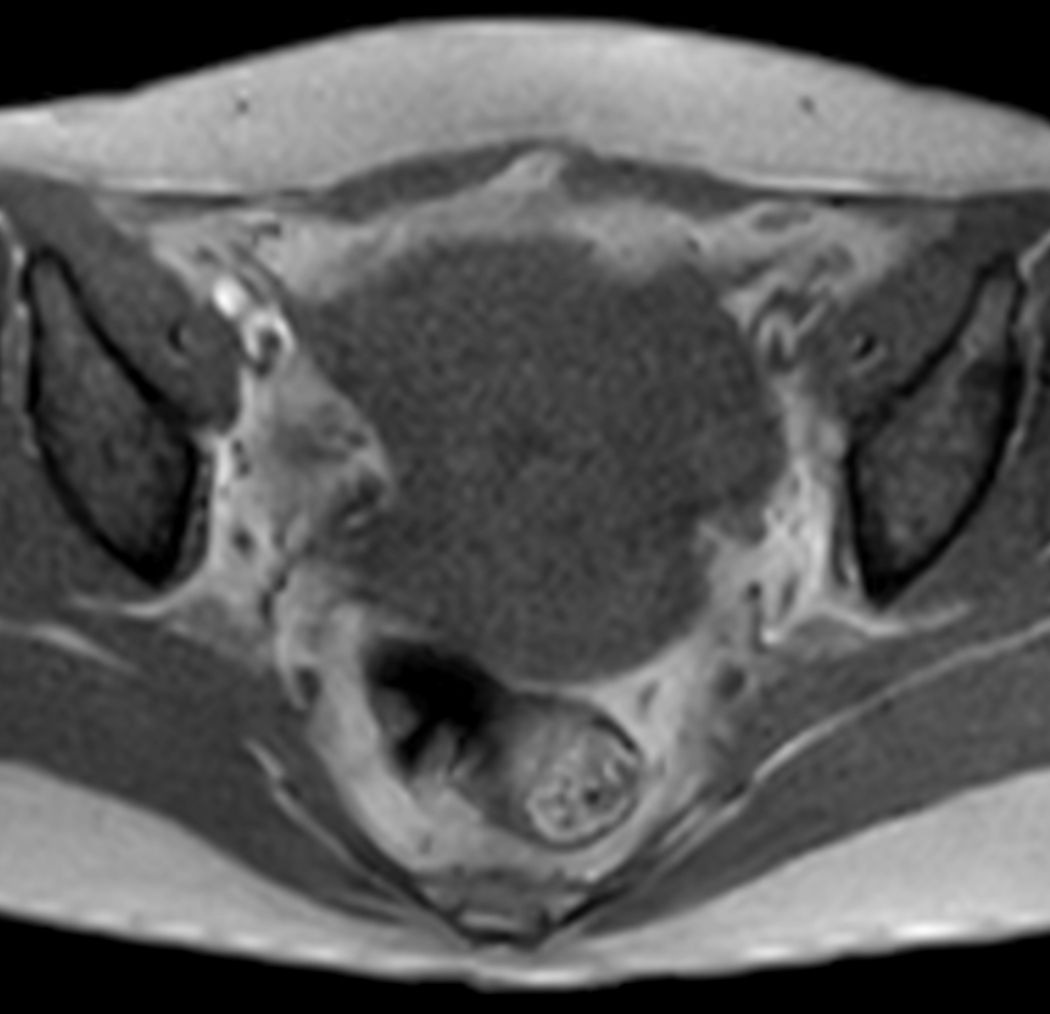

Axial MultiVane XD - T1w TSE

Axial mDIXON XD - T1w FFE (Water only)